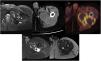

Case 2A 65-year-old male with a history of high-grade lymphoma, immunosuppression and septic arthritis in the left hip operated on two years previously. He presented with left hip pain that had notably worsened in the previous day.

MRI (Fig. 2A) and CT scans (Fig. 2B) were performed, revealing a heterogeneous collection compressing the sciatic nerve in the proximal third of the leg. Given the clinical stability, conservative management was determined and evolutionary studies were performed over two years, during which time the collection maintained a similar volume, modifying internal signal probably due to haemoglobin degradation. The patient was admitted for pain and a PET-CT scan was performed (Fig. 2C), revealing a peripheral hypermetabolic component. A chocolate-coloured fluid was evacuated and a partial resection was performed, along with capsular dissection to the point where it was severely adhered to the sciatic nerve.

A) MRI heterogeneous collection with hypodense capsule (→). B) CT: predominantly hypodense collection, with peripheral enhancement (→). C) PET: peripheral hypermetabolic component observed. D and E) Post-surgical MRI: less voluminous collection and increased signal hyperintensity on T2 (*), corresponding to partial resection and new CEH formation.

An MRI study one month after surgery (Fig. 2D) showed a collection with a smaller volume yet similar characteristics, compatible with partial resection and a newly formed CEH. Subsequently, a total hip prosthesis was fitted due to chronic osteomyelitis. No further imaging tests were performed given the patient’s positive progress.